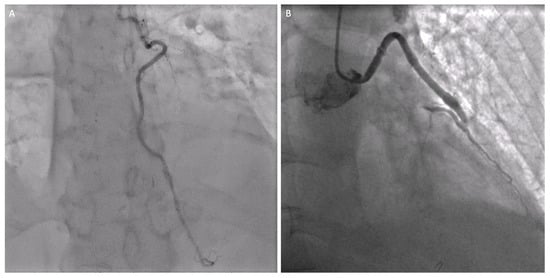

- Absence of calcification of the ascending aorta, allowing the execution of the proximal anastomosis (Figure 4A).

| LIMA angiographic patency at staged PCI (n° of pts, %) | 10 (100%) |